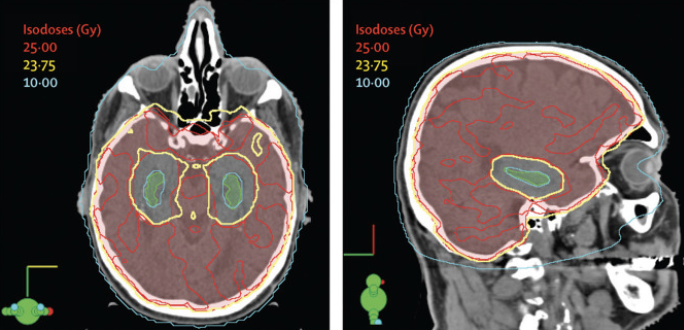

What is PCI?

- Prophylactic cranial irradiation (PCI) may be used for patients with higher stages of SCLC to reduce the risk of brain metastases.

- You may not be eligible for PCI if: you are older than 60, you have neurocognitive impairment or have a poor general performance status.

- It is important to note that approximately 60% of patients with tumours located in the thorax develop metastases in the brain (Suwinski, 2021).

- Your oncologist will order MRI or PET images of your brain to look for any signs of cancer that is present but difficult to detect via imaging.

- If your oncologist decides that you do not need PCI, you will still need multiple follow-up MRIs to ensure no spread has occurred.

- This is what a typical PCI setup looks like:

Image Credit: The Lancet

Doses Used for PCI

- Current standard dose from Suwinski (2021):

- 25 Gy delivered over 10 fractions, given once daily (each fraction = 2.5 Gy).

How is my Body Affected by PCI?

- Decline in memory may be observed at approximately 1 year post-irradiation (Suwinski, 2021).

- Fatigue, appetite loss, nausea, and leg weakness for up to 3 months due to temporary swelling of brain tissue as an acute response to radiation (Edelman, 2020).

- However, neuropsychological impairment could be connected to the cancer itself or to treatment given before PCI (Péchoux et al., 2016).

- Improvements have been made to significantly reduce dose to critical structures such as the hippocampus.

- Whole-brain irradiation for brain metastases while sparing the hippocampus was associated with the preservation of memory and quality of life and these practices may be introduced into PCI to lessen the side effects and improve quality of life (Péchoux et al., 2016).

- Hippocampus plays an important part in brain injury repair, so sparing this portion of the brain from radiation is important.